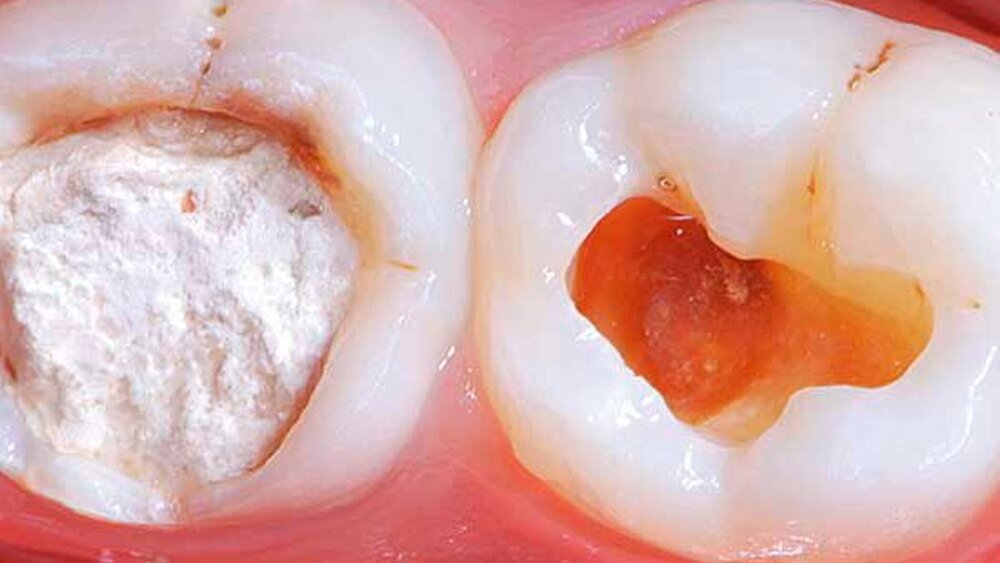

Die flowable BFK enthalten in der Regel signifikant weniger Füllkörper und weisen ein niedrigeres E-Modul sowie eine geringere Oberflächenhärte und eine höhere Abrasion auf. Das bedeutet, dass sie mit einer 2-mm-Deckschicht eines normalen Komposits okklusal überdeckt werden müssen.

Schlussfolgerungen: Basierend auf den vorhanden In-vitro- und In-vivo-Daten können die meisten BFK als gleichwertig zu den herkömmlichen Kompositen im kaulasttragenden Seitenzahnbereich eingestuft werden. Jedoch müssen die flowable BFK mit einem konventionellen Komposit oder einem höher viskösen BFK abgedeckt werden. Die Inkrementtechnik (Schichttechnik) bleibt der Goldstandard – bis mehr klinische Langzeitdaten mit fünf Jahren und mehr vorliegen.